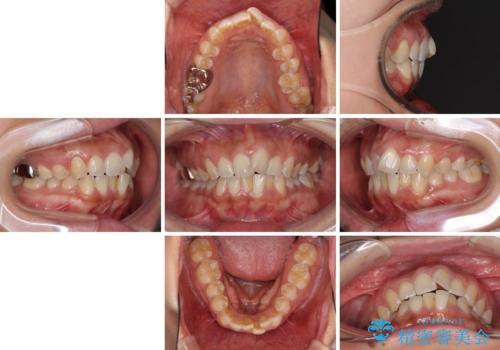

インビザラインによる狭窄歯列の拡大矯正

- 前歯のデコボコを治したいとのことで来院された患者様です。

上下顎ともに歯列全体の後方移動と側方拡大、IPR(歯と歯の間を削る)によってデコボコが解消するように設計し、インビザラインにより治療を行うこととしました。

後方移動に際し、上下の親知らずは4本とも抜歯することとしました。

治療途中で関西に転勤となってしまったため、東京に出張で来るタイミングに合わせて治療を進めることになりました。そのため、治療期間が長くなってしまいましたが、無事に仕上げることができました。